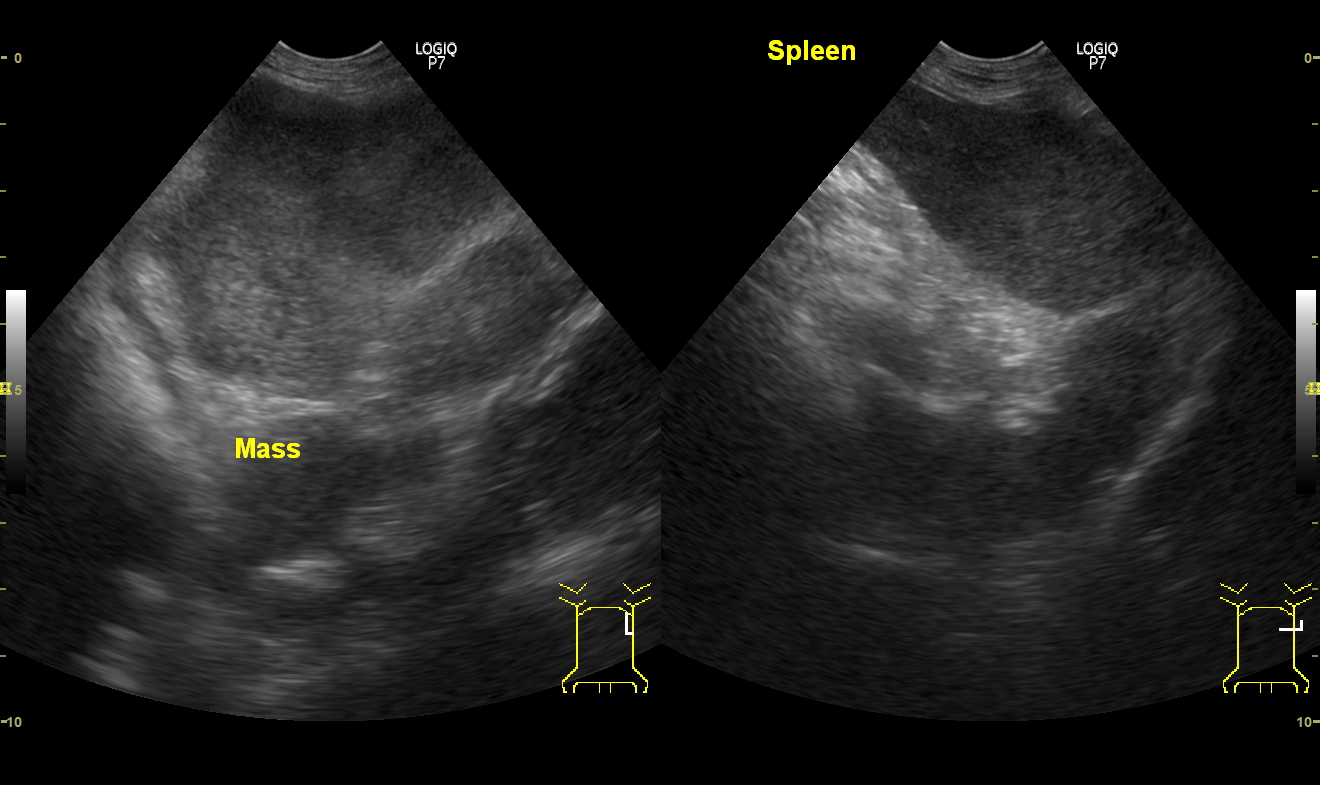

脾臓のリンパ腫(肝脾T細胞型リンパ腫)の症例